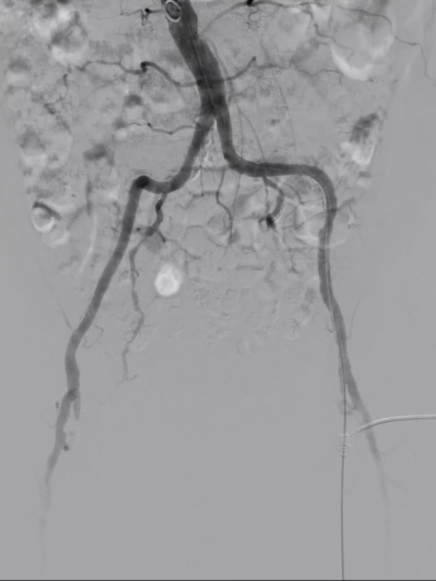

管腔准备与支架植入

预扩张:使用球囊扩张病变段,造影提示长段限流性夹层,需支架覆盖

治疗模式:因股腘动脉直径<4.5mm,选择DCB(药物涂层球囊)+BMS(裸金属支架)联合方案;

支架选择:在DCB扩张导管进行管腔准备后,植入2枚5mm INNOVA支架,其优势在于尾端定位精准,尤其适合累及开口或分叉的病变。